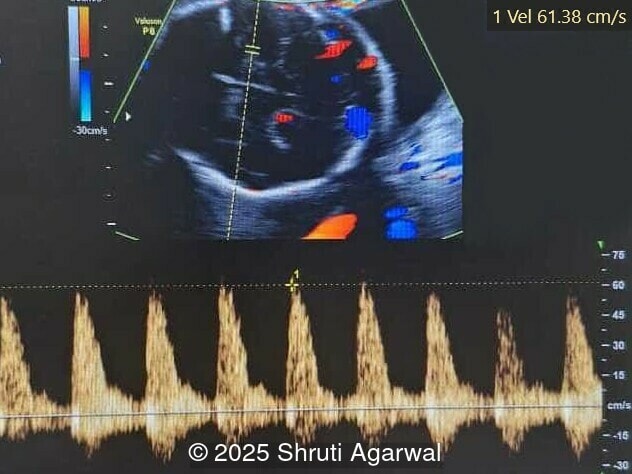

- Image 1,2: Large placental tumor is identified with internal vascularity

- Image 5: normal cardiac inflow

- Image 6,7: Mitral regurgitation

- Image 9: Middle cerebral artery peak systolic velocity >1.5MOM suggesting fetal anemia

Prenatal diagnosis depends on ultrasound, however, chorangioma can cause an increase in maternal serum alpha-fetoprotein [3]. Ultrasound examination reveals a hypo- or hyperechoic, well-circumscribed mass, which is usually located underneath the chorionic plate near the umbilical cord insertion, and often protrudes into the amniotic cavity. Color Doppler demonstrates large vascular channels around and within the tumor [6,9]. In cases of giant chorangiomas, echocardiography should be performed to assess cardiac function and measure fetal middle cerebral artery peak systolic velocity for diagnosis of fetal anemia. Regular ultrasounds with Doppler studies are used to monitor tumor size, fetal growth, amniotic fluid volume, and signs of fetal anemia or heart failure. The frequency of exams is based on tumor size and associated complications. With small tumors, assessment may occur every 3-4 weeks, whereas in large tumors, the ultrasound scan may be done every 1-2 weeks [3]. These regular assessments can diagnose conditions that require intervention, such as polyhydramnios, hydrops, or hemolytic anemia.